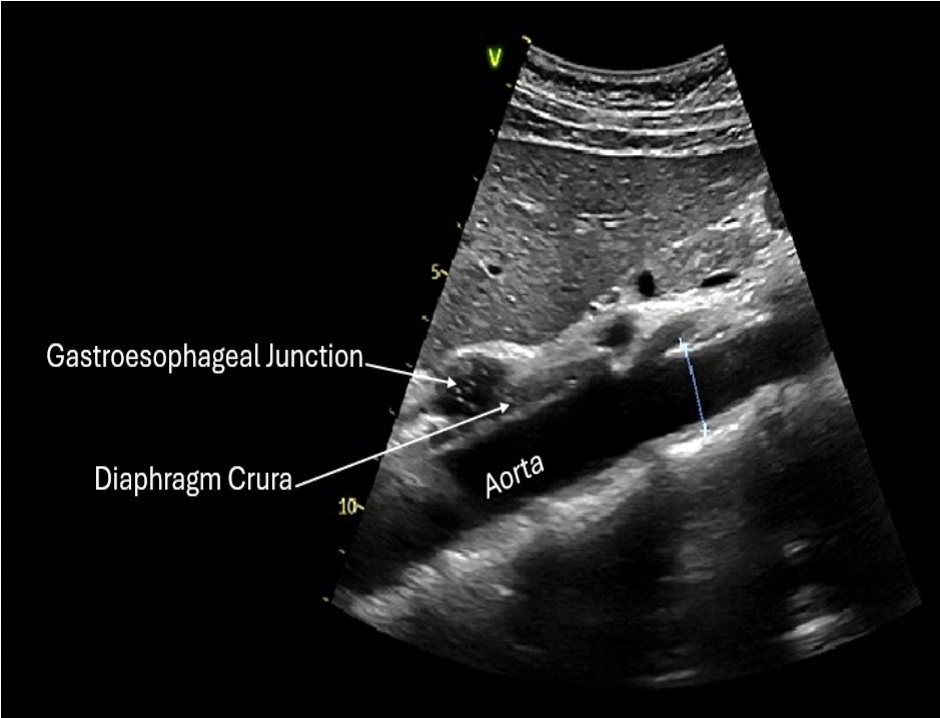

The gastroesophageal junction is best seen in the ______ plane, anterior to the aorta and posterior to the left lobe of the liver.

A. longitudinal

B. The opening by which the esophagus communicates with the stomach

The esophagus extends from the pharynx to the cardiac orifice of the stomach.